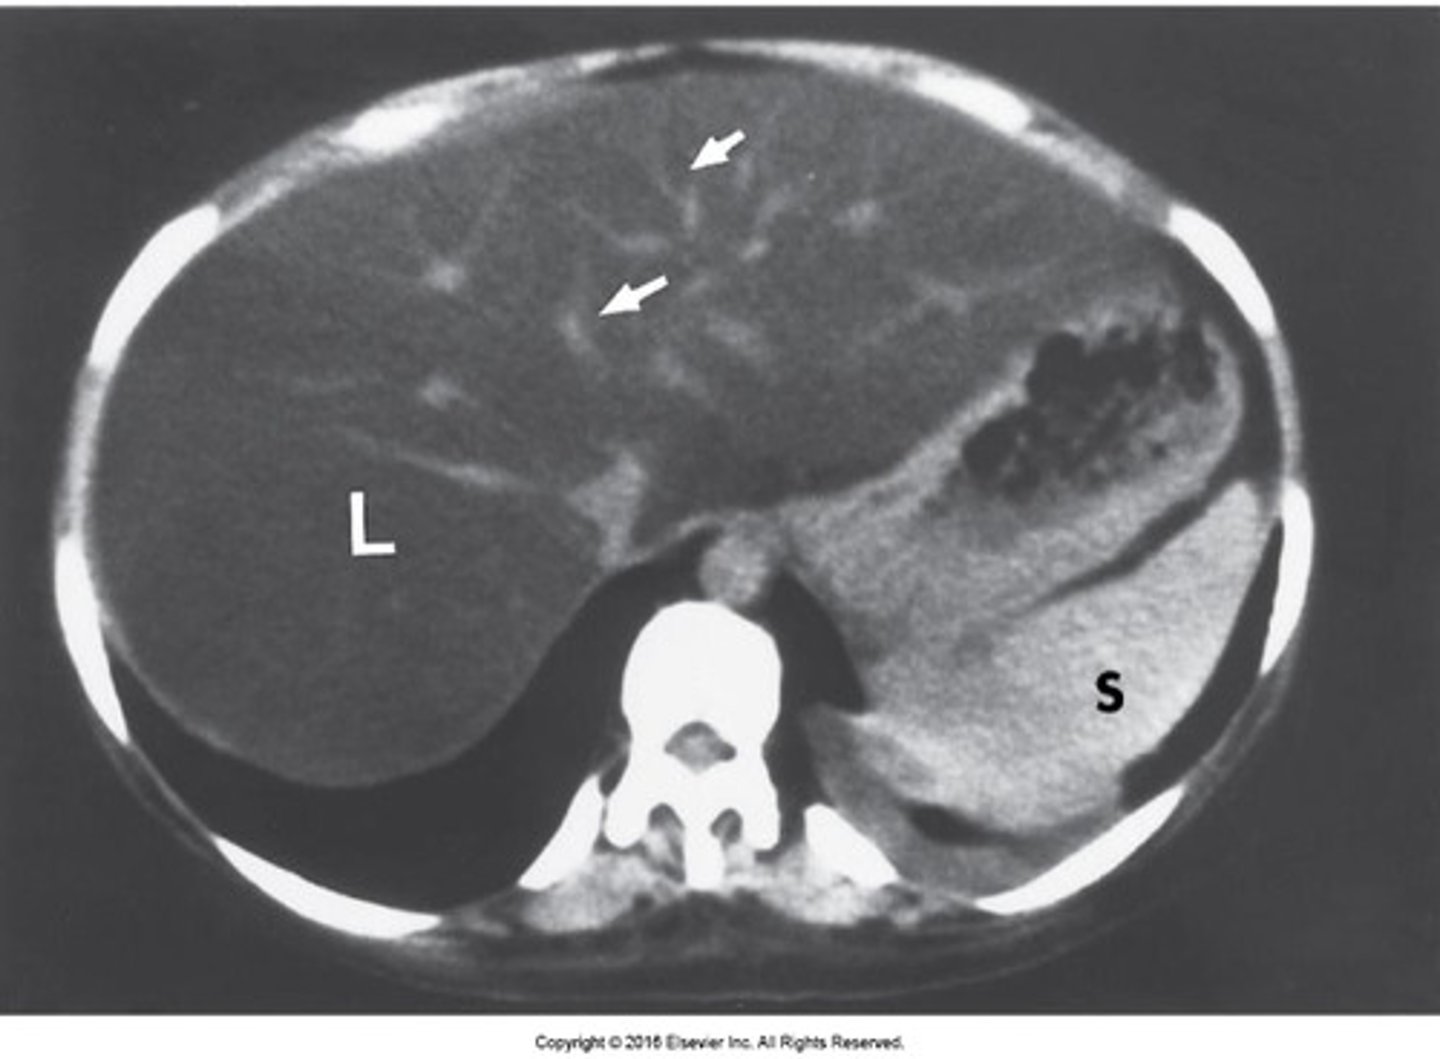

spleen

most highly vascular organ, most injured organ in blunt trauma

CT is diagnostic study of choice

Tx: mostly non-surgical

splenic laceration

hemorrhage and hematoma present, dark fluid is blood surrounding spleen